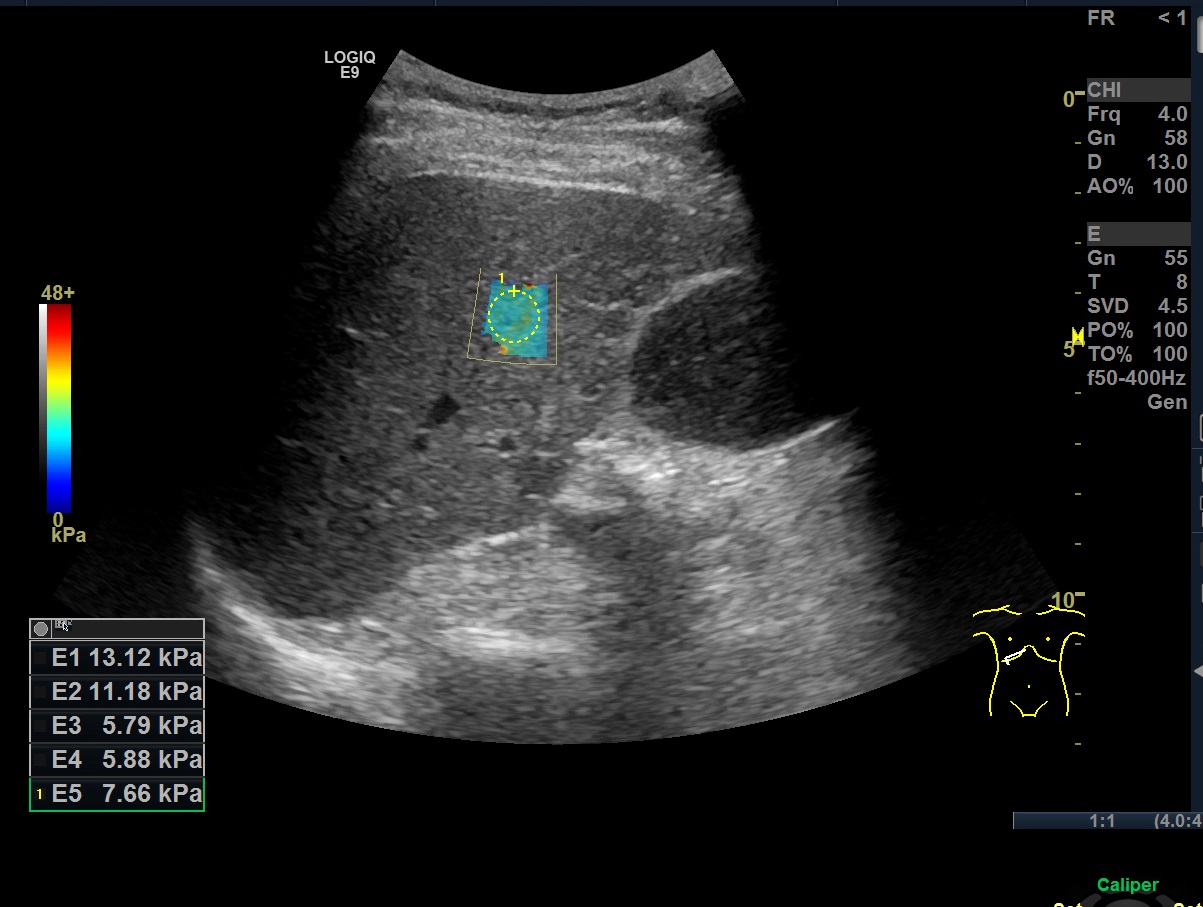

위의 영상은 며칠 전 오른쪽 복통을 호소해서 간초음파를 위해 오신 분의 탄성초음파 측정값입니다. 총 다섯번을 측정했는데, 첫번째와 두번째 값이 매우 높게 측정이 되었고, 나머지 세번의 측정은 정상에 가까운 수치가 나왔습니다. 측정 시 자세나 여타 조건은 큰 문제가 없었는데 이렇게 큰 편차가 난 이유는 환자분이 배가 아픈걸 참지 못해 측정하는 순간 배에 힘을 주셨기 때문입니다.

처음에는 환자분이 힘을 준걸 모르고 정말로 간섬유화가 진행된 분이었는가 착각했었는데, 탐촉자를 잡고 지탱하기 위해 환자분의 배 위에 닿아있던 오른손 손목의 감촉에서 배에 힘을 주고 있는걸 눈치챘었습니다. 힘을 빼라고 해도 무의식적으로 힘을 주고 있던건데, 생각만큼 세게 힘을 준것도 아닌데 이렇게 stiffness 값이 높게 측정이 되더군요.

곧바로 최대한 힘을 빼달라고 말씀드리고, 손으로 힘이 빠진걸 확인하고 난 후에 측정한 값은 모두 정상범주 안에 들어와있었습니다.